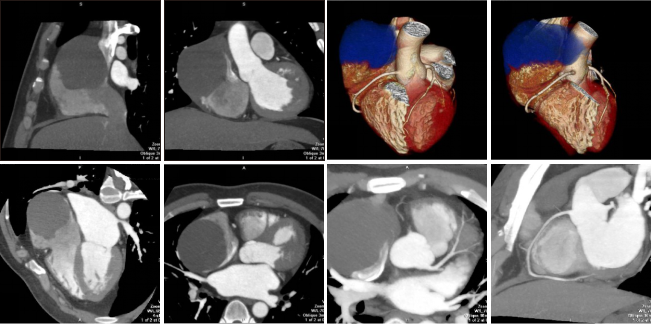

病例二 男,30歲, 右心房占位性病變,心功能Ⅱ級(jí),心律失常,心房纖顫, 平均心室率92次/分。

術(shù)前CT檢查:

右心房增大,其內(nèi)可見(jiàn)占位性病變,通過(guò)獨(dú)有的三維染色后處理,可以對(duì)腫瘤進(jìn)行染色, 以便于確定腫塊與心臟血管及其他周圍結(jié)構(gòu)的關(guān)系。

心臟彩超及食道超聲可見(jiàn)右房?jī)?nèi)囊性占位病變;室間隔及左室壁厚度正常高限;雙房大; 左室收縮功能正常; 彩色血流示: 各瓣膜未見(jiàn)病理性返流。

腫瘤病理結(jié)果與CT檢查顯示的大小、 形態(tài)相符合。

術(shù)后CT檢查:

術(shù)后可見(jiàn)右房形態(tài)正常, 心臟其余各結(jié)構(gòu)未見(jiàn)明顯異常。

640層寬體探測(cè)器CT實(shí)現(xiàn)了3 20排譜黃金寬體探測(cè)器1 6 cm的 超寬覆蓋范圍, 與2 7 ms超 快時(shí) 間 分 辨 率 的 完 美 結(jié) 合 , 可 以 實(shí) 現(xiàn) 微 劑 量 高 清 全 景 電 影 成 像 。 特 別 是 在 冠 脈 檢 查 上 , 可 以 實(shí) 現(xiàn)一次心跳下的心臟冠脈檢查, 實(shí)現(xiàn)復(fù)雜心率情況下高清冠脈成像的100 % 檢查成功率。

此外,強(qiáng)大的后處理功能,能提取心臟冠脈,明確腫瘤大小、形態(tài)、表面特征、位置及三維展示與周圍結(jié)構(gòu)的關(guān)系,還能提供心功能等各項(xiàng)參數(shù),以便臨床對(duì)心臟情況做一個(gè)充分的評(píng)估,術(shù)前充分設(shè)計(jì)好方案尤為重要。